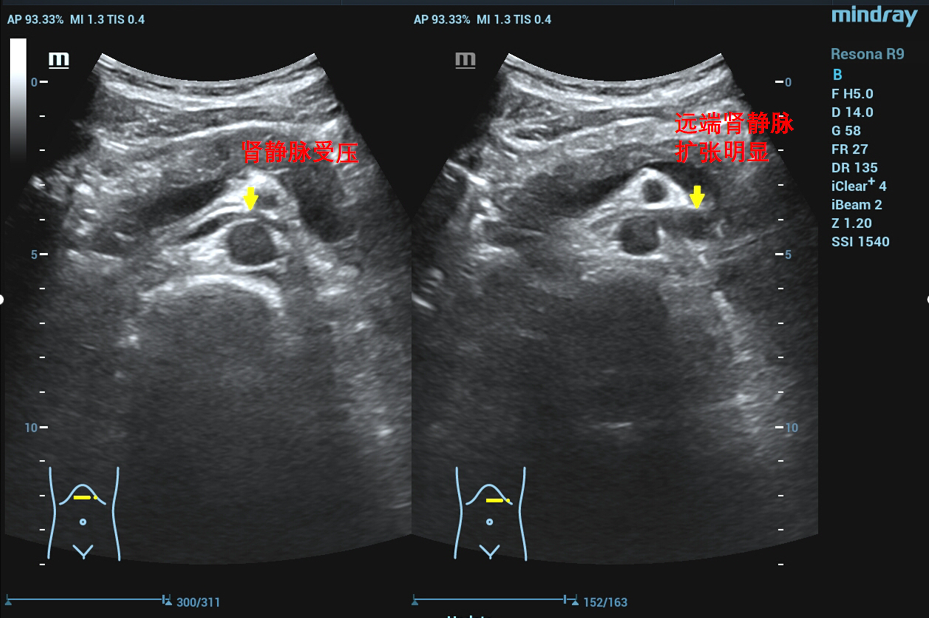

患者于两年前无明显诱因出现肉眼血尿及排尿疼痛,偶有左侧腰部疼痛,无明显精索静脉曲张,曾于基层医院就诊行CT等检查提示左肾静脉压迫综合征,也就是胡桃夹综合征。为进一步的诊治前来樱花动漫 就诊,经过泌尿外科三病区详细的检查和判断,该患者左肾静脉胡桃夹现象比较明显,临床症状比较重。泌尿外科三病区对患者的病情进行反复的讨论,并与患者的家属和患者本人充分沟通后决定行手术治疗。

在泌尿外科三病区柯昌兴主任、杨博伟副主任医师、李宇航博士团队的精心准备和密切配合下,顺利为患者完成“腹腔镜(3D)下左肾静脉外支架置入术”。术中,见左肾有3根动脉,其中一根动脉绕行并压迫左肾静脉(术前阅片已确认),左肾静脉入肠系膜上动脉与腹主动脉夹角处,其周围纤维条索较多,此处左肾静脉明显变窄,离断纤维条索后此处左肾静脉明显增宽,充分游离左肾静脉近端至下腔静脉,远端至“其中一根动脉绕行并压迫左肾静脉”处,离断左性腺静脉和肾上腺中央静脉。柯昌兴主任团队成功放置一根6cm长带外支撑环的人工血管固定在患者左肾静脉外面,为受压的左肾静脉支撑起一条“生命通道”,提供持久的支撑力对抗肠系膜上动脉和腹主动脉的压迫。整个手术非常顺利,耗时约3小时,出血约10毫升。术后3天,患者康复出院,且腰痛、血尿等术前临床症状明显缓解,手术效果非常显著。

胡桃夹综合征,也称胡桃夹现象。是指左肾静脉回注下腔静脉过程中,需穿经由腹主动脉和肠系膜上动脉形成的夹角内受到挤压而引起的血尿、蛋白尿和左腰腹疼痛等临床症状。又称为左肾静脉受压综合征。近年来随着诊疗技术的发展。胡桃夹综合征引起的血尿发病率呈逐渐上升趋势,越来越受到临床的关注。

正常情况下,腹主动脉与肠系膜上动脉所形成的夹角为45度到60度,并为脂肪、淋巴、纤维结缔组织等填充,而左肾静脉并不受压。因为某些情况下可使夹角变窄,左肾静脉受压,导致左肾瘀血、肿大,以及左生殖腺静脉瘀血、曲张。